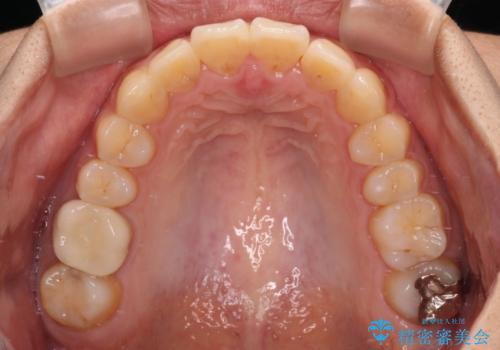

- 前方に傾斜した上下の前歯を気にして来院された患者様です。

唇の閉じにくさや横顔のシルエットが気になるような突出感ではなかったため、インビザラインを用いて、歯列の遠心移動とIPR(歯と歯の間を削る)により前歯の傾斜を改善していくこととしました。

スムーズに終了すると思われましたが、インビザライン矯正独特の奥歯が咬み合わない状態が続き、更には遠方へ転居されたこともあり、治療期間は長引いてしまいました。